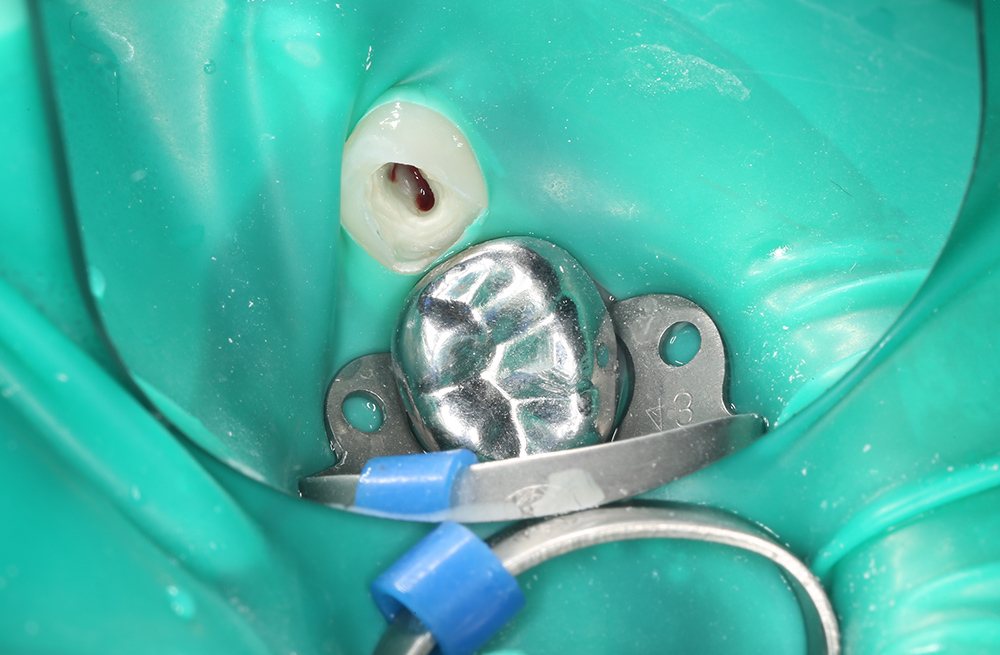

Сохранение зуба при обратимом пульпите